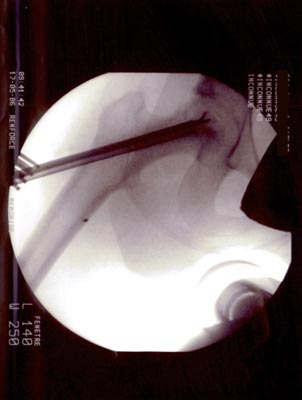

Technique opératoire Le trocart est introduit par voie pertrochantérienne et suit le trajet de la vis. Sa position dans la tête fémorale et dans la nécrose est repérée sous amplificateur de brillance de face et de profil. Une petite pince à séquestre retire les tissus fibreux et nécrosés circonférenciellement après repérage. Un lavage au sérum bétadiné complète le curetage. La moelle osseuse est prélevée (à l'aide du trocart de Mallarmé) sur la crète iliaque selon la technique classique. La moelle recueillie est d'autant plus riche en cellules souches qu'elle a été aspirée par petites fractions (2 ml). Ceci permet de réduire le degré de dilution par le sang périphérique. Elle est ensuite mélangée extemporanément avec le biomatériau. En général : 5 ml pour 5 cc de corail naturel. Sous contrôle Rx., le greffon est introduit à l'aide d'un trocart jusque dans la tête au niveau de la zone curetée : L'appui-contact avec 2 C.B est immédiat. Faut-il mettre en décharge avec traction et combien de temps ? Il ne sera possible de répondre à cette question que lorsque l'on saura avec précision la durée des phases de déminéralisation-reminéralisation du composite biomatériau-moelle osseuse aboutissant à de l'os néo- formé mécaniquement solide. C'est aux fondamentalistes de nous apporter la réponse.

OSTEONECROSE ASEPTIQUE de la H.D. Intervention en mai 2006